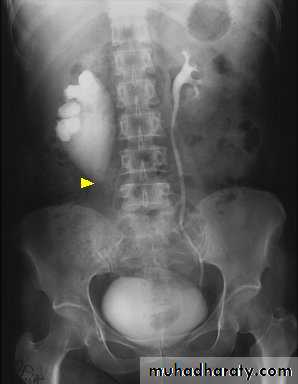

Failure of contrast to pass to ureters due to both sided mid ureteric stones

LT sided upper Ureteric stones

Bilateral HU + HN